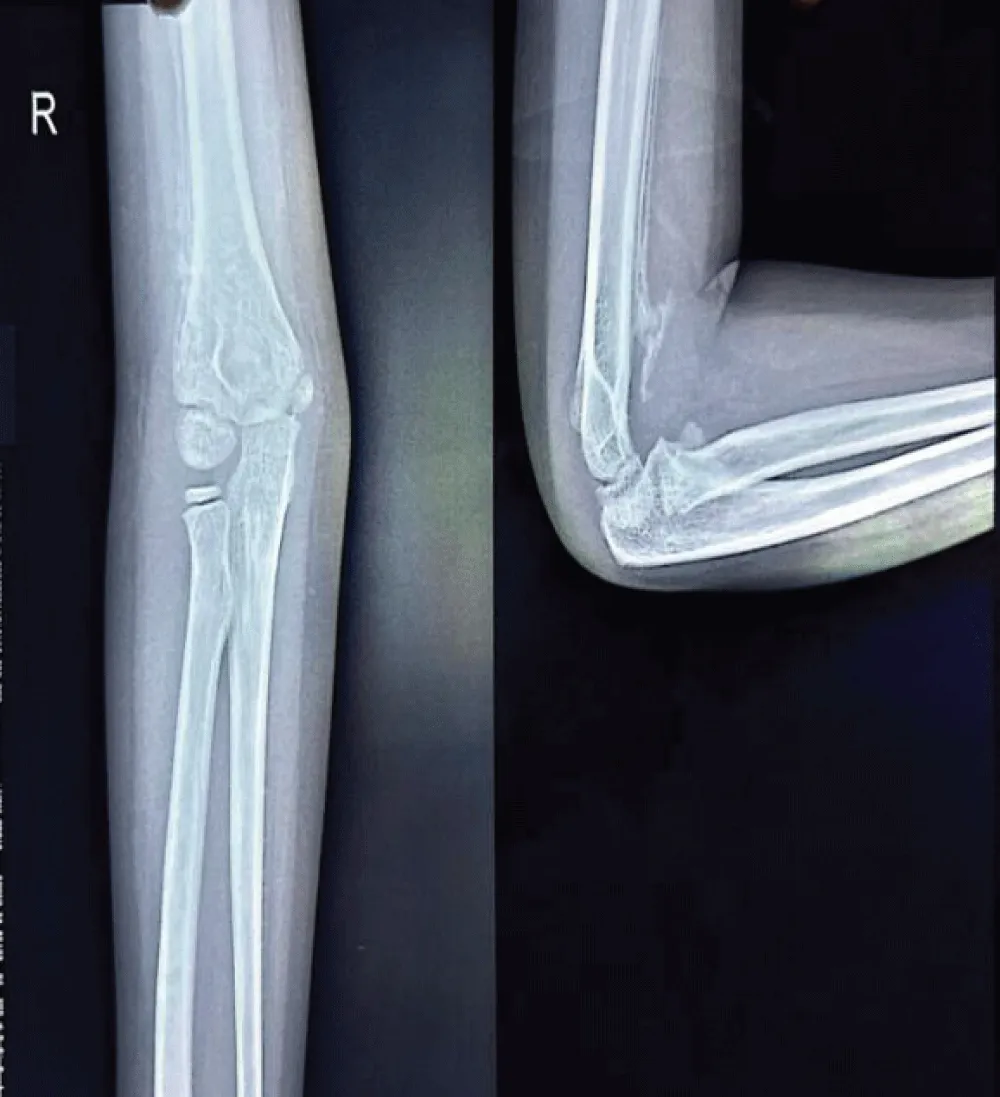

However, the child continued to experience persistent pain and stiffness in the elbow region, progressively limiting the range of motion. This prompted another hospital visit, during which an X-ray of the right elbow was obtained (Figure 5). Subtle calcific changes-early signs of heterotopic ossification-were present but went unnoticed. Physiotherapy was initiated under the assumption of post-immobilization stiffness. However, within a few days of physiotherapy, the patient developed worsening stiffness and a painful, enlarging subcutaneous lump in the elbow region.

Radiograph of the elbow joint revealed a well-defined calcified mass parallel to the humerus, with a convex shape extending along the supracondylar region with the classical features of heterotopic ossification. The patient guardians declined further advanced imaging studies, including MRI, citing personal reasons. Consequently, the diagnosis of Myositis Ossificans Traumatica was made based exclusively on radiographic findings.